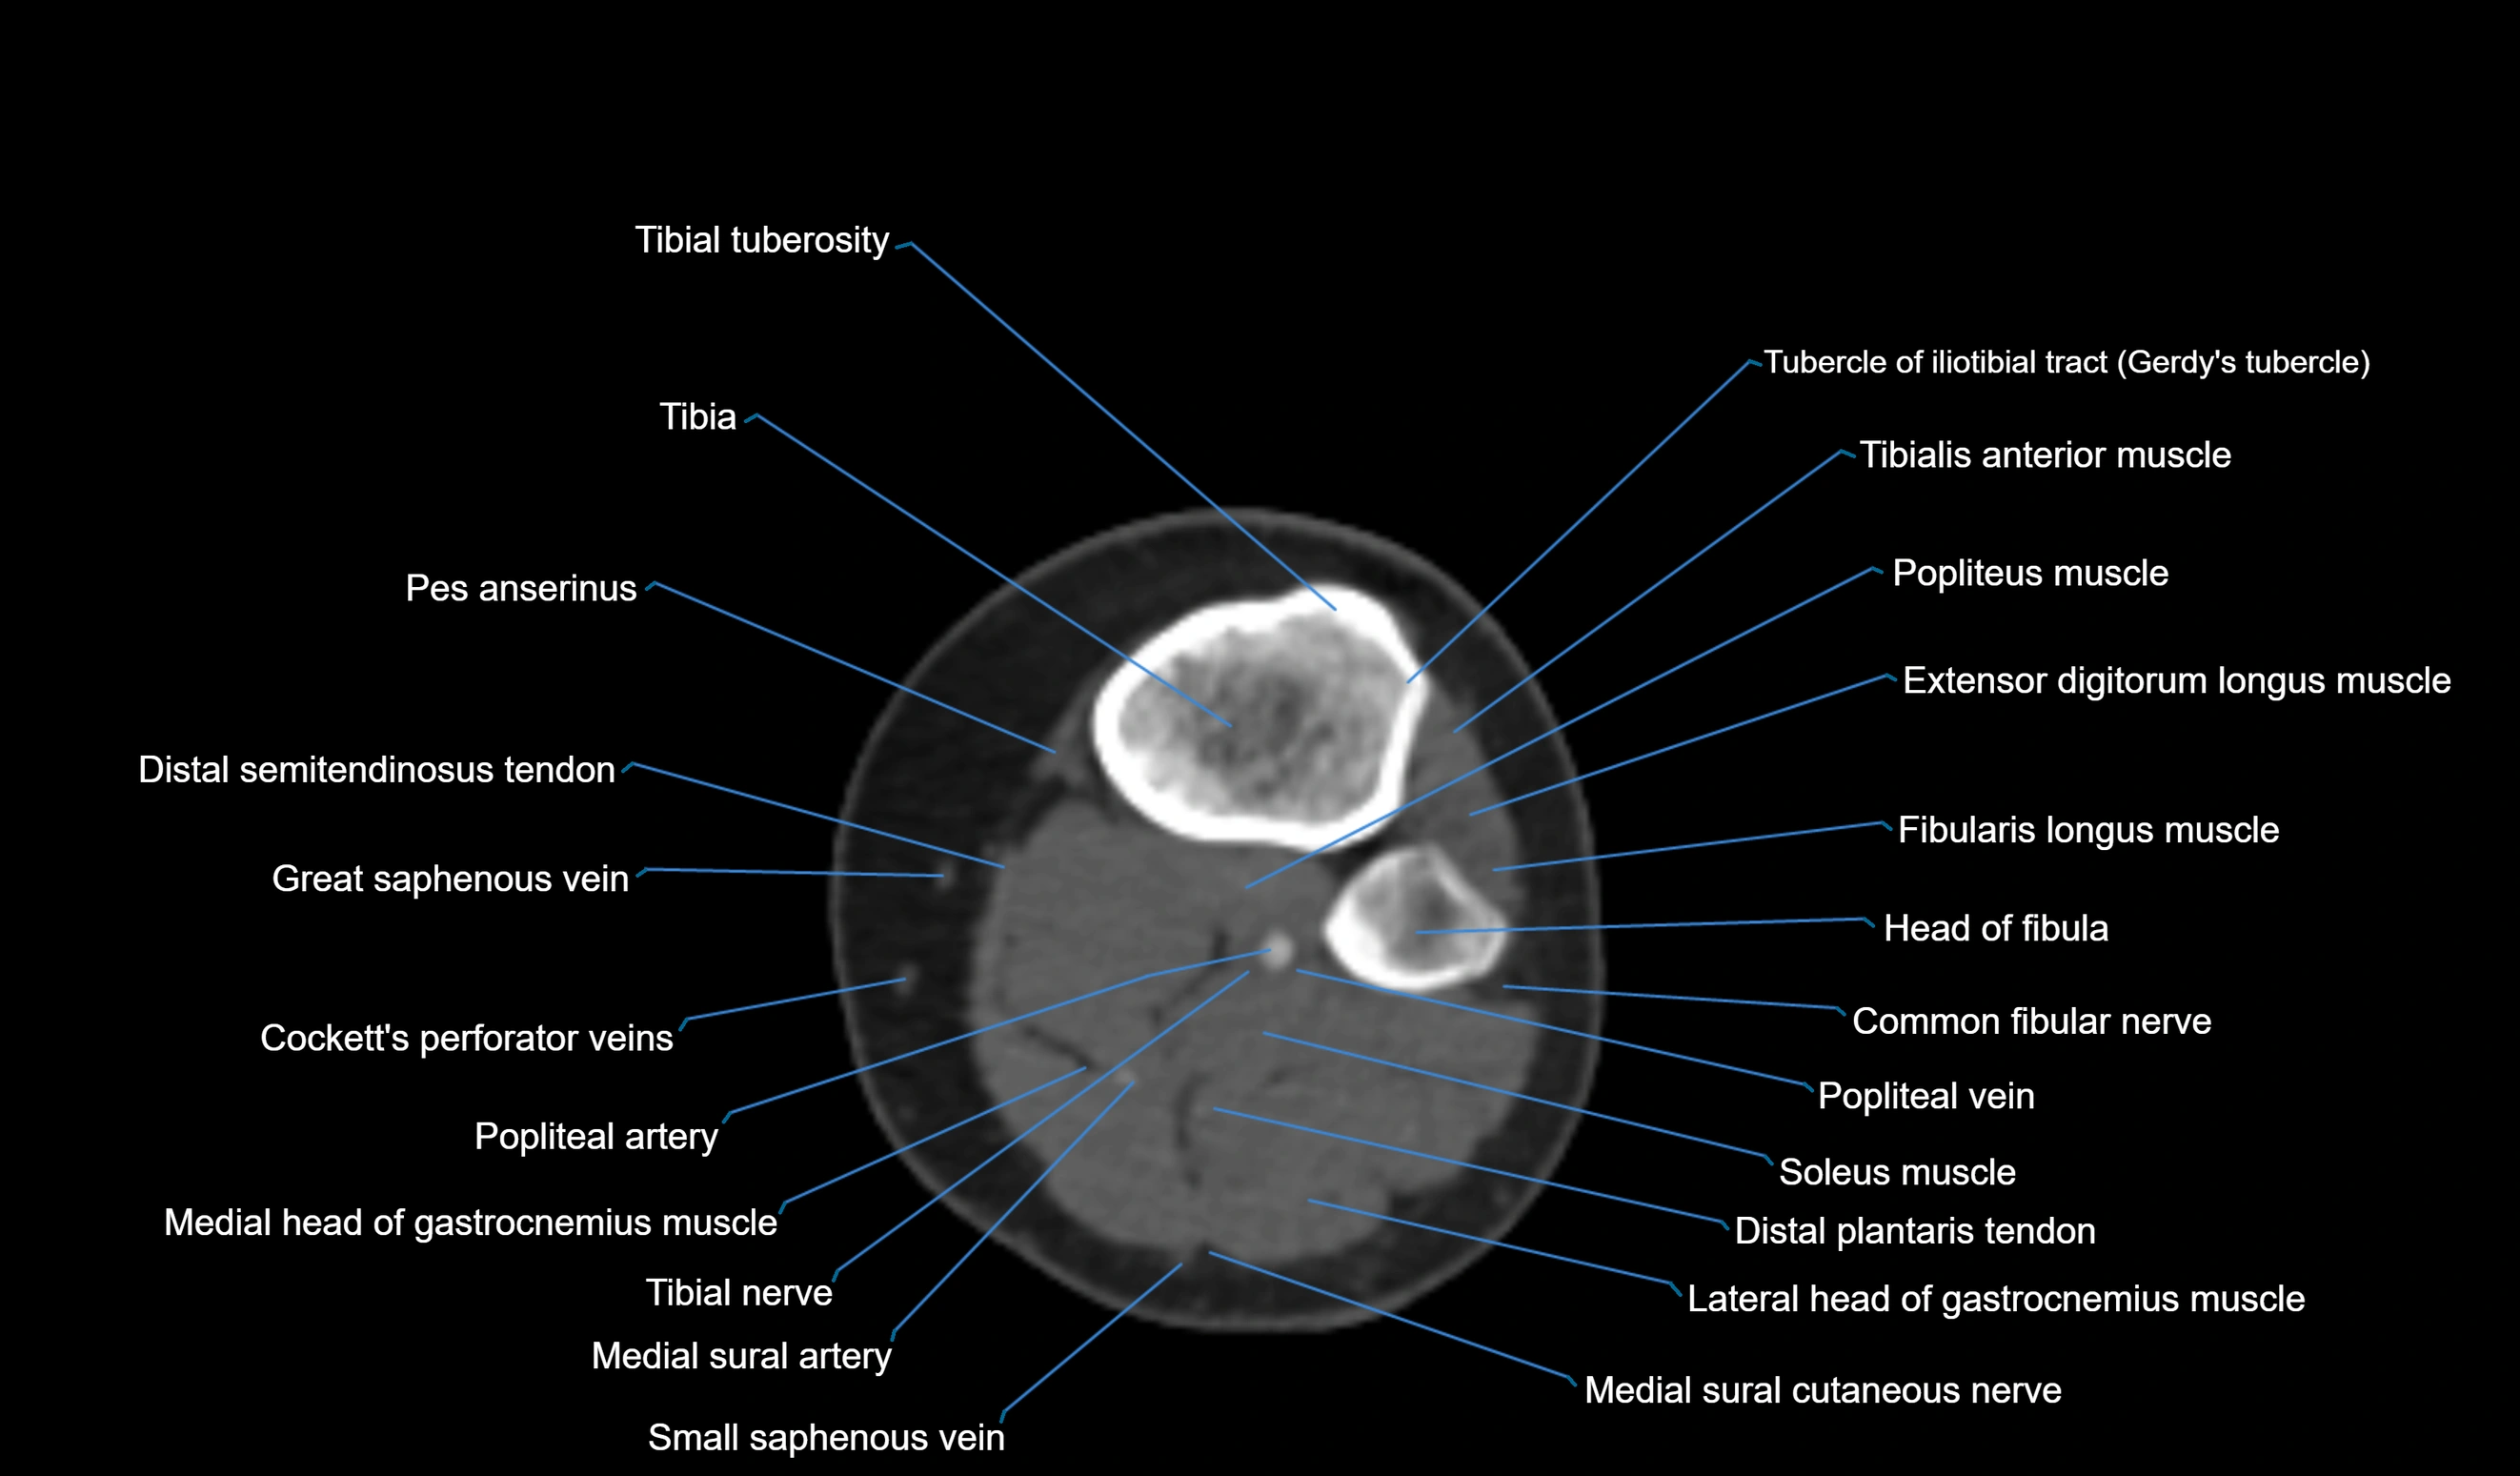

- Extensor digitorum longus muscle

- Fibularis longus muscle (peroneus longus muscle)

- Head of fibula

- Lateral head of gastrocnemius muscle

- Medial head of gastrocnemius muscle

- Popliteal artery

- Popliteal vein

- Soleus muscle

- Tibia

- Tibial tuberosity

- Tibialis anterior muscle

- Tubercle of iliotibial tract